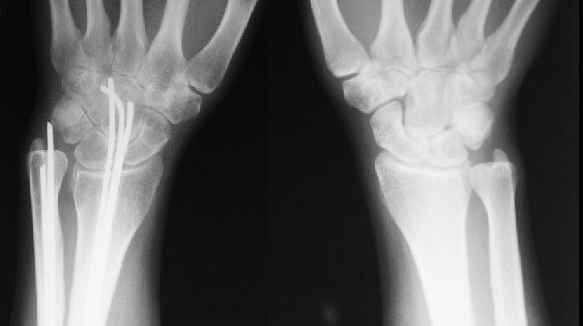

Сравнительные снимки в приложении

> Укорочение во многом связано с угловой деформацией, после устранения которой, увеличится и длина луча. Сделайте для сравнения прямую рентгенограмму л/з сустава на здоровой стороне

Помимо отсутствия физиологической кривизны лучевой кости, есть еще и рекурвация, поэтому, после устранения углов длина вряд ли увеличится.